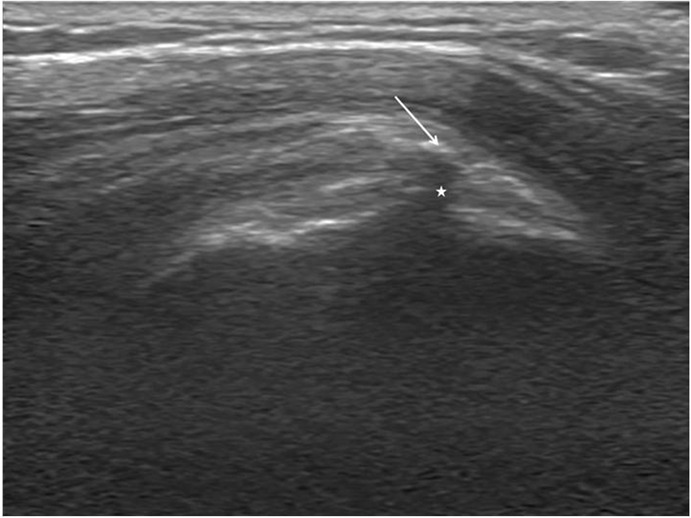

Fig. 2.

Sonographic finding of the partial-thickness rotator cuff tear. The arrow indicates the partial-thickness rotator cuff tear.